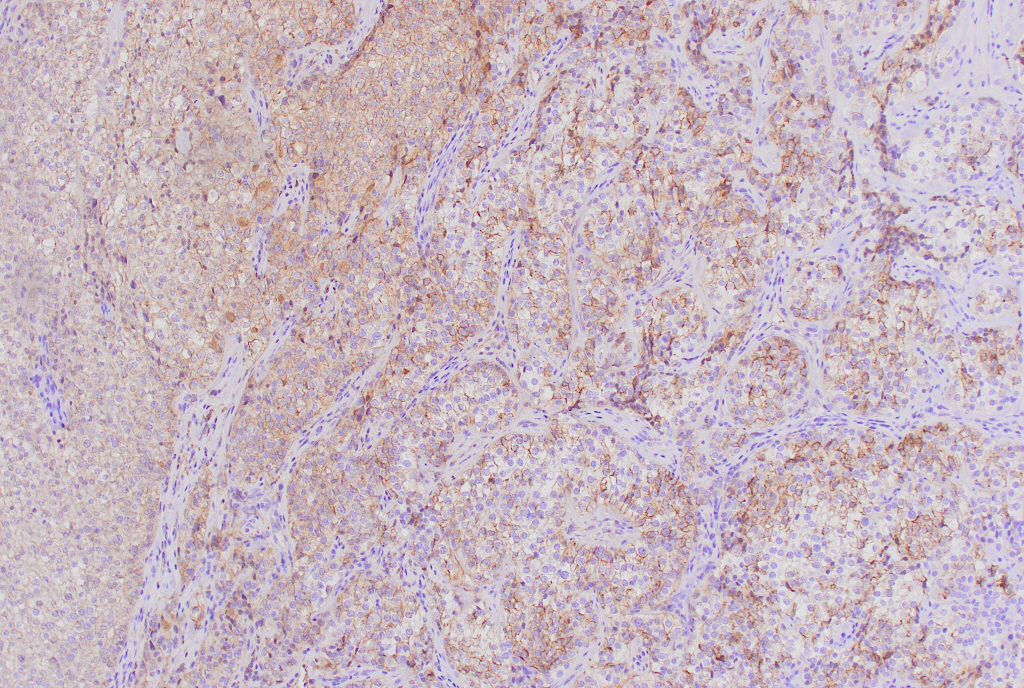

手術後の組織診の免疫染色にてカルシトニン陰性、クロモグラニンAとシナプトフィジン陽性の結果より、副甲状腺癌と診断された症例であった。

HE カルシトニン クロモグラニン シナプトフィジン